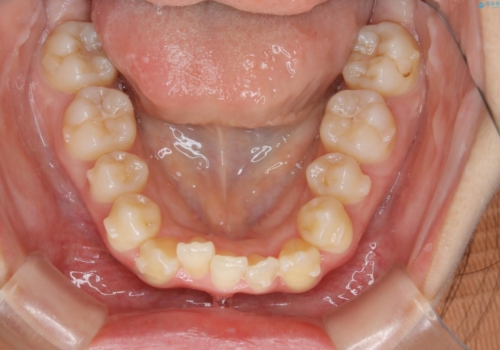

下顎前歯の先天欠損と上顎前歯のクロスバイト:インビザライン治療

元々下の前歯が1本欠損しており、上下の噛み合わせや、歯のサイズバランスを考慮しながら治療を行いました。

下顎切歯が1本欠損しているため、上顎前歯部を少しずつストリッピングして、上下の噛み合わせ、バランスの向上を図りました。